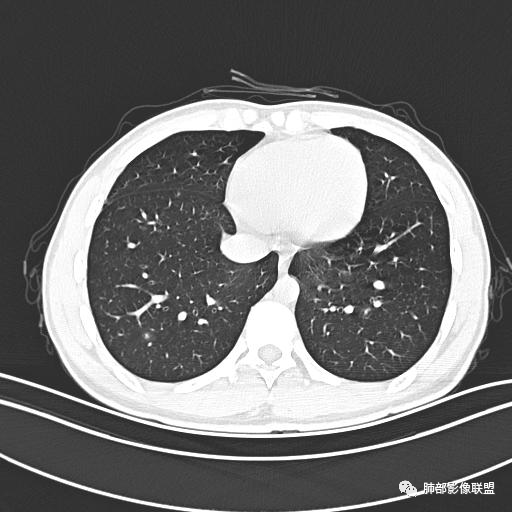

男,19岁

主  诉:发热、全身皮疹2天。

现病史:患者源于2天前受凉后出现发热,最高体温为38.5℃,且颜面部出现少量皮疹,无鼻塞、流涕、咳嗽、咳痰,未在意而未作特殊处理,次日全身皮疹逐渐增多至全身,伴轻度瘙痒,在当地卫生所给予抗病毒、抗感染治疗(具体用药不详)体温有所下降,但皮疹无明显消退,无腹痛、头痛,食欲无明显减退,为进一步诊治,遂于今日急来我院求治,患者目前精神尚可,体力正常,食欲正常,睡眠正常,体重无明显变化,大便正常,排尿正常。

小强:青年,发热,皮疹;双肺散在结节,周围磨玻璃,点晕征,疱疹病毒感染,鉴别荚膜组织胞浆菌,结核。 大雄:青年,急性起病,发热伴全身皮疹2天,抗病毒治疗体温有下降。双肺随机分布大小不等类圆结节,“点晕征”。考虑水痘-疱疹病毒(VZV)血播询问接触史,查体皮疹分布以及形态基本可诊断。 王开金江津中心医院呼吸科:青年男性,起病急,病程短,以发热,皮疹为首发症状,感染指标以单核细胞升高为主,胸部ct双肺多发结界,周围有晕,点晕表现,随机分布,同意於老师意见,水痘疱疹病毒血流感染累及肺。 王秀仙:双肺多发大小不等结节,周围有晕,边缘模糊,呈点晕征表现。青年,急性起病,发热伴全身皮疹2天,抗病毒治疗体温有下降。考虑疱疹病毒。鉴别荚膜组织胞浆菌。 傅昌瑜:19岁男性,发热、全身皮疹2天,单核细胞增高,双肺多发结节,结节边缘见边界不清磨玻璃影。点晕征+发热、全身皮疹+单核细胞增高——考虑水痘-带状疱疹病毒肺炎。 一切∮随缘:年轻男性,发热,皮疹两天,实验室,CRP,PCT增高,影像:双肺多发散在磨玻璃结节,边界欠清,大小不等,呈点晕征改变,以血管束周围分布为主,局部血管束略增粗,其它无明显改变,考虑:1:病毒性肺炎(水痘疱疹病毒?不知道皮肤有无改变)2:真菌(组织胞浆菌,血管侵袭性肺曲霉)3:GPA4:寄生虫(实验室没有看到嗜酸细胞增高) 赵山河:双肺散在结节,周围有晕,边缘模糊,呈点晕征表现。青年,急性起病,发热伴全身皮疹2天,抗病毒治疗体温有下降。考虑水痘—疱疹病毒感染。洪桥爱:青年男性,发热、皮疹2天,伴瘙痒,皮疹于面部首发,之后进展至全身,虽然没有对皮疹进行描述,但是从出疹时间及皮疹进展情况,伴瘙痒,应该就是个水痘患者;CT提示双肺随机分布结节影,部分结节伴有边界不清晕征,考虑水痘血播肺。 刘强:年轻男性,急性起病,皮疹,发热,抗感染治疗体温下降,说明有效。影像表现为散在点晕征,感染类疾病谱(疱疹病毒,真菌,结核),结合年龄,皮肤皮疹,考虑水痘-疱疹病毒性肺炎。 小兜:男性,19岁,发热皮疹两天,颜面部至全身,CRP,降钙素及单核增高。CT示双肺散在小结节,周围伴磨玻璃影,点晕征,考虑为水痘-带状疱疹病毒(varicella-zoster virus,VZV)肺炎 必有路:青年,皮疹+发热+“点晕征”→水痘-疱疹病毒(VZV) 许慧良:青年男性患者,发热、皮疹2天,体温最高38.5℃,第3天皮疹扩展至全身,伴瘙痒,胸部CT:双肺多发随机分布的小结节,结节周边见边界模糊的晕征,考虑水痘病毒感染流心明智:男,19,急性起病,发热伴全身皮疹2天。出疹顺序头→全身,抗病毒有效。胸部CT:两肺多发大小不等类圆形实性小结节影,随机分布,结节周围环绕GGO,边界模糊,呈点晕征。出疹特点是关键,未提示。考虑:血播病毒性肺炎,水痘-疱疹病毒?麻疹?鉴别荚膜组织胞浆菌、TB、血管炎、寄生虫等。 浪迹天涯:病灶多为5-10mm大小结节,结节周围可见磨玻璃样的晕环,常多发,可分布于肺内任何区域,考虑水痘—带状疱疹病肺炎如果短时间内有新的一个区域浸润,更加能说明,